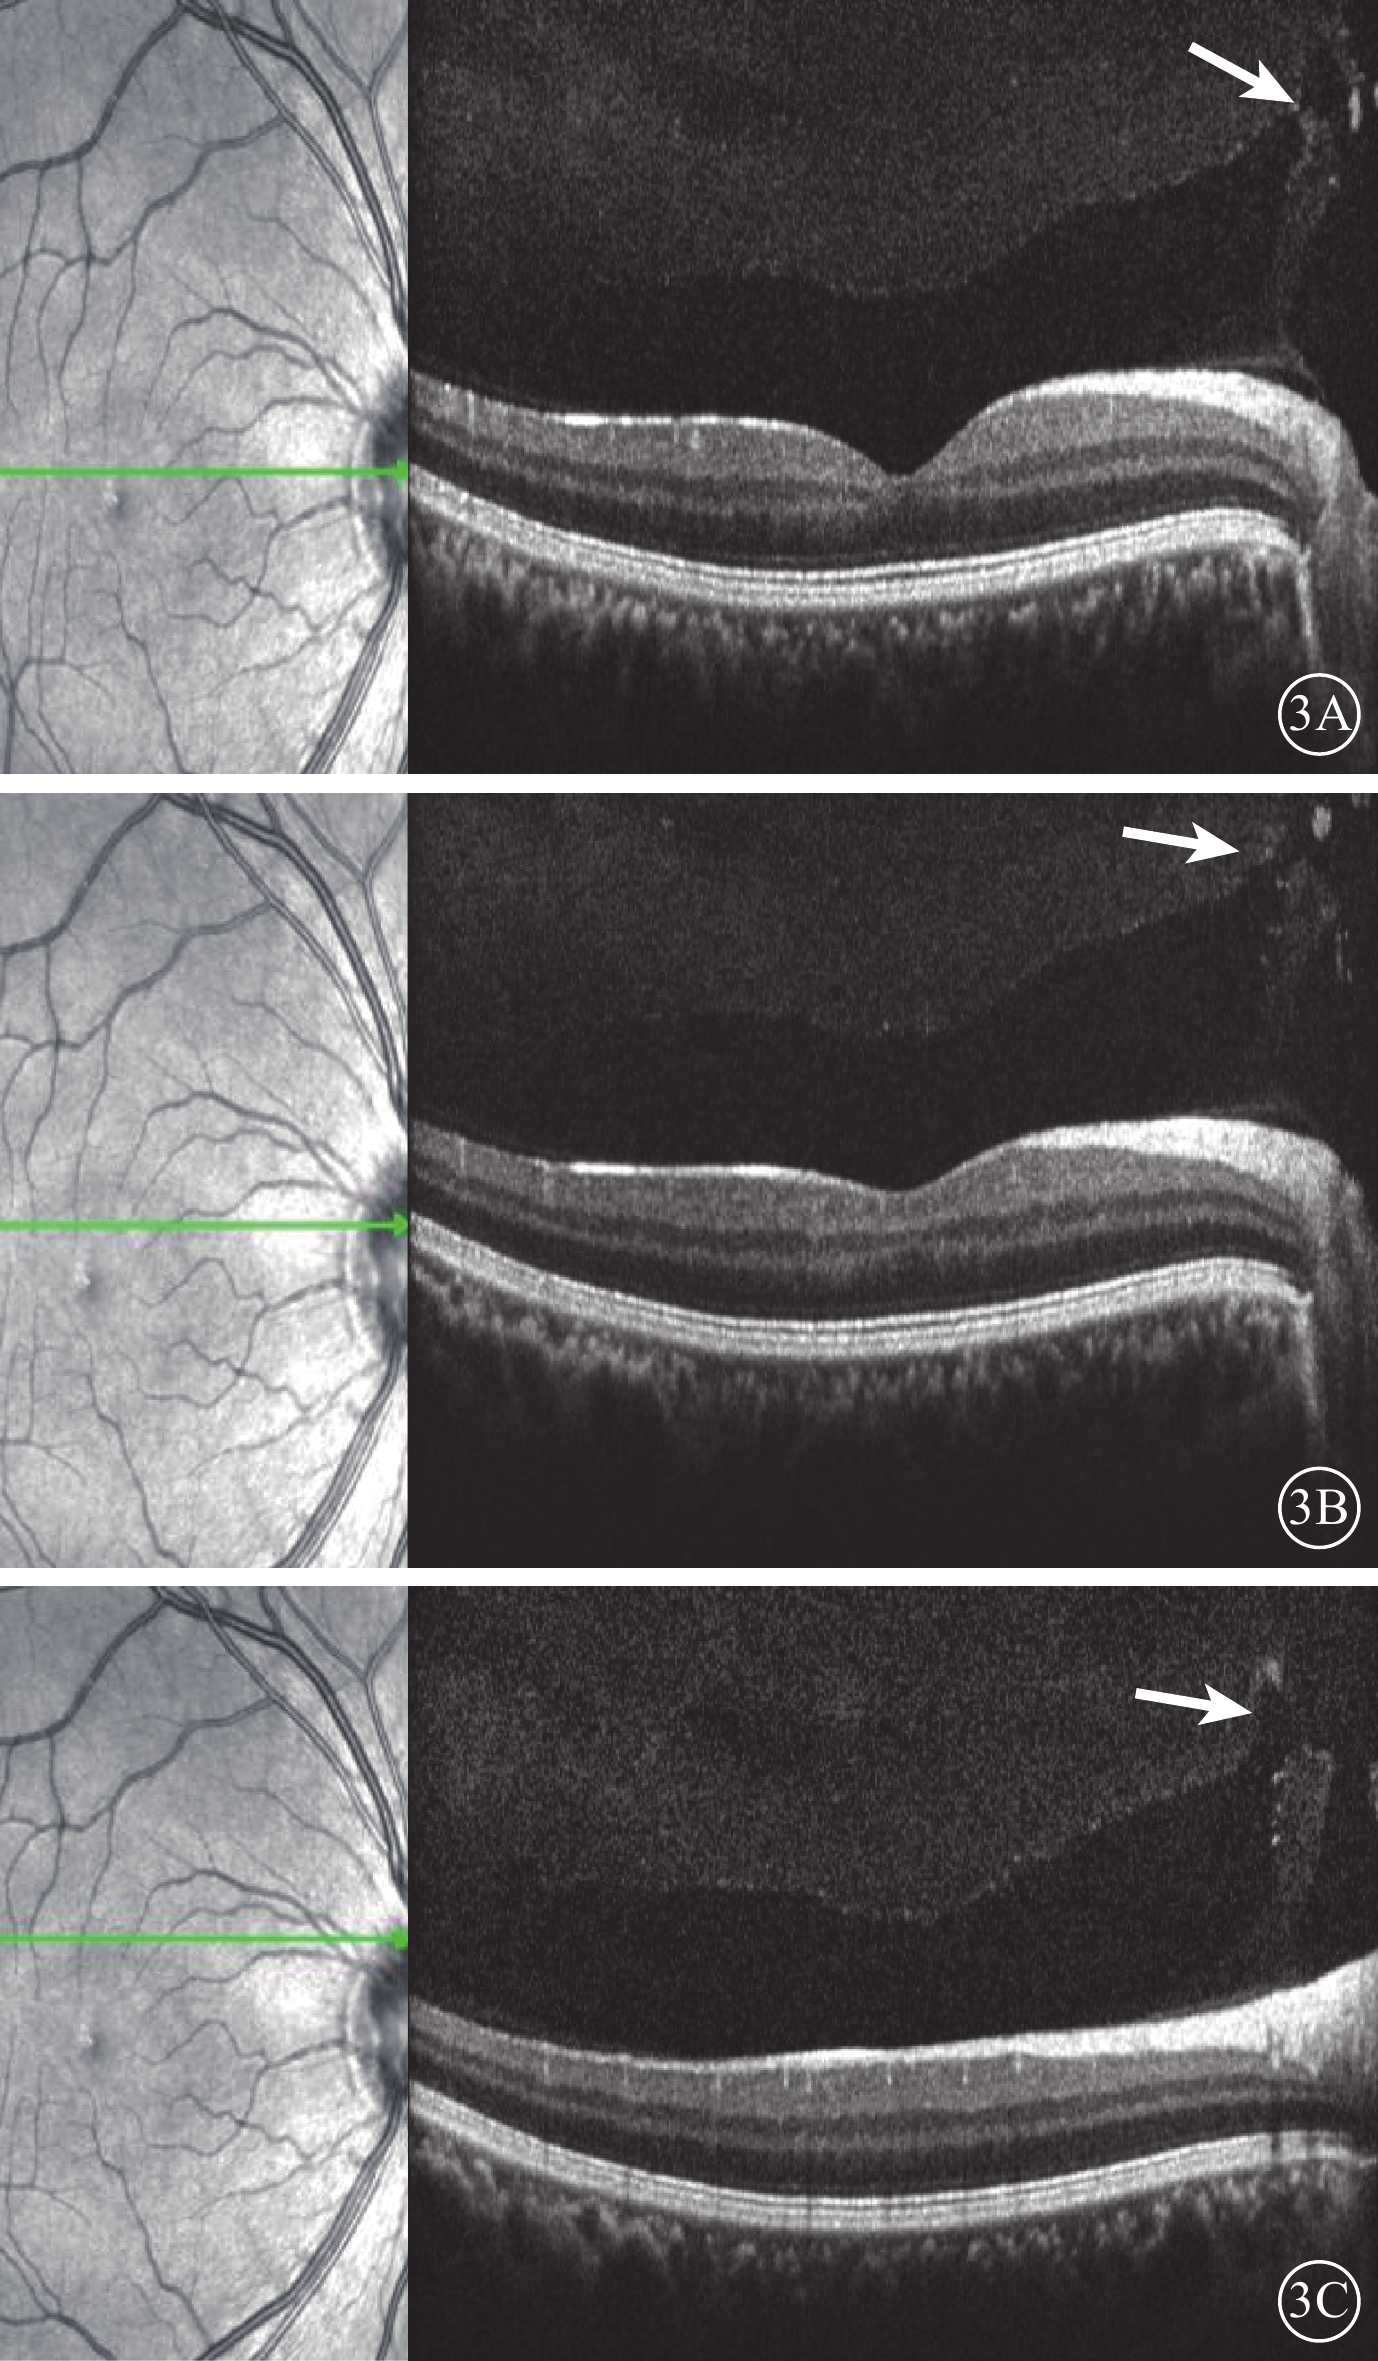

圖3

受檢眼SD-OCT像。左圖為掃描方向和部位;右圖為檢查結果。3A示PPVP與Martegiani區之間出現一小縫隙(白箭);3B示縫隙擴大,可見兩者之間出現連通(白箭);3C示PPVP與Martegiani區之間明顯連接通道(白箭)

圖3

受檢眼SD-OCT像。左圖為掃描方向和部位;右圖為檢查結果。3A示PPVP與Martegiani區之間出現一小縫隙(白箭);3B示縫隙擴大,可見兩者之間出現連通(白箭);3C示PPVP與Martegiani區之間明顯連接通道(白箭)

SD-OCT檢查,所有受檢眼常規檢查均未觀察到PPVP。后極部玻璃體掃描模式所采集的圖像可見PPVP結構清晰,表現為黃斑區前弱反射船形腔隙,前界為玻璃體膠原,后界為玻璃體皮質(圖2)。所有受檢眼PPVP鼻側存在一弱反射的無凝膠區域(Martegiani區),兩者之間有一隔膜將其分開。其中,單線掃描可見PPVP與Martegiani區之間存在連接通道(圖2)68只眼(66.0%);多線掃描可見所有受檢眼PPVP與Martegiani區存在連接通道,通道在某些層面出現(圖3)。PPVP前可見一個或多個黃斑上囊(圖2)16只眼(15.5%),其中黃斑上囊與PPVP之間相互連通(圖4)5只眼。PPVP伴玻璃體后脫離(PVD)(圖5)9只眼。采用FDI掃描模式進行檢查的21只眼,視網膜、脈絡膜成像清晰度較好,但玻璃體成像清晰度較差(圖4)。60只眼的PPVP平均最大水平距離為(6 895.7± 872.8)μm,平均垂直距離為(524.1±173.9)μm。

圖3

受檢眼SD-OCT像。左圖為掃描方向和部位;右圖為檢查結果。3A示PPVP與Martegiani區之間出現一小縫隙(白箭);3B示縫隙擴大,可見兩者之間出現連通(白箭);3C示PPVP與Martegiani區之間明顯連接通道(白箭)

圖3

受檢眼SD-OCT像。左圖為掃描方向和部位;右圖為檢查結果。3A示PPVP與Martegiani區之間出現一小縫隙(白箭);3B示縫隙擴大,可見兩者之間出現連通(白箭);3C示PPVP與Martegiani區之間明顯連接通道(白箭)